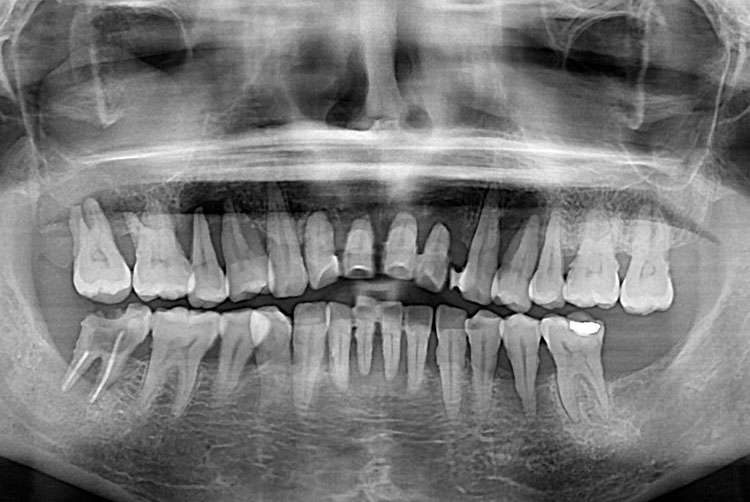

치료전 : 2018-07-20

김소완_후.jpg

치료후 : 2018-09-27

세종치과는 많은 환자와 다양한 케이스를 바탕으로 항상 편안한 임플란트 수술을 제공하고자 노력하고,

오래동안 튼튼히 쓸 수 있는 임플란트 수술을 가장 큰 목표로 삼고 있습니다.